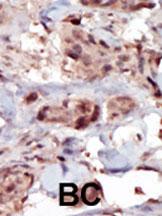

Formalin-fixed and paraffin-embedded human cancer tissue reacted with the primary antibody, which was peroxidase-conjugated to the secondary antibody, followed by AEC staining. This data demonstrates the use of this antibody for immunohistochemistry; clinical relevance has not been evaluated. BC = breast carcinoma; HC = hepatocarcinoma. |